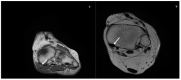

Adult acquired flatfoot deformity (AAFD) is a disorder caused by repetitive overloading, which leads to progressive posterior tibialis tendon (PTT) insufficiency. It mainly affects middle-aged women and occurs with foot pain, malalignment, and loss of function. After clinical examination, imaging plays a key role in the diagnosis and management of this pathology. Imaging allows confirmation of the diagnosis, monitoring of the disorder, outcome assessment and complication identification. Weight-bearing radiography of the foot and ankle are gold standard for the diagnosis of AAFD. Magnetic Resonance Imaging (MRI) is not routinely needed for the diagnosis; however, it can be used to evaluate the spring ligament and the degree of PTT damage which can help to guide surgical plans and management in patients with severe deformity. Ultrasonography (US) can be considered another helpful tool to evaluate the condition of the PTT and other soft-tissue structures. Computed Tomography (CT) provides enhanced, detailed visualization of the hindfoot, and it is useful both in the evaluation of bone abnormalities and in the accurate evaluation of measurements useful for diagnosis and post-surgical follow-up. Other state-of-the-art imaging examinations, like multiplanar weight-bearing imaging, are emerging as techniques for diagnosis and preoperative planning but are not yet standardized and their scope of application is not yet well defined. The aim of this review, performed through Pubmed and Web of Science databases, was to analyze the literature relating to the role of imaging in the diagnosis and treatment of AAFD.